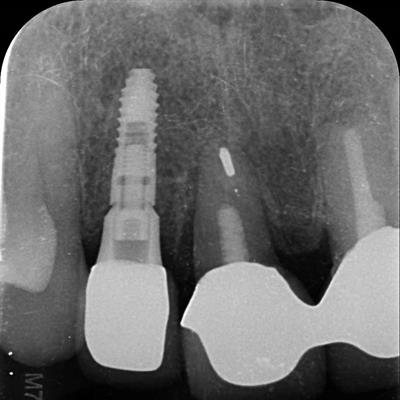

Dental Implants

• Dental X-Ray Photo

• Digital X-Rays (faster results)